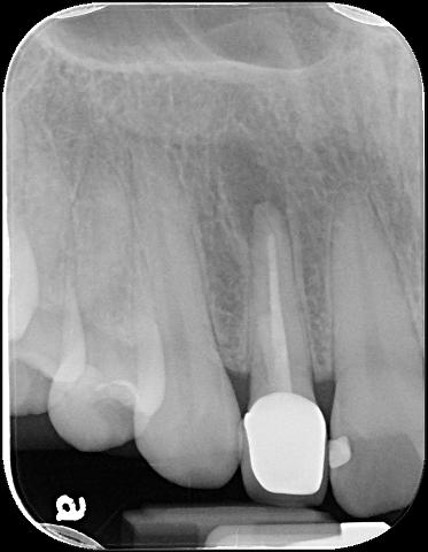

治療前,根尖病變